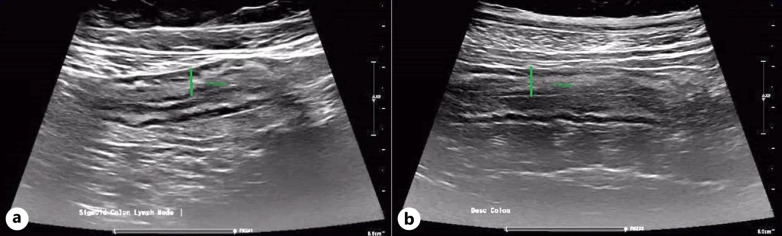

Introduction: Acute severe ulcerative colitis (ASUC) represents a medical emergency associated with high mortality and morbidity. While corticosteroids are the primary treatment, cases that are unresponsive often require rescue therapy with either infliximab or cyclosporine to reduce the rate of colectomy. Janus kinase inhibitors, such as tofacitinib and upadacitinib, are a highly efficacious therapy with rapid induction of clinical response in moderate to severe ulcerative colitis (UC). Limited data are available on its use on ASUC. We present the first case utilizing upadacitinib as sequential medical rescue therapy in ASUC as well as intestinal ultrasound as a useful tool for disease and response monitoring.

Case presentation: A 69-year-old female who presented with corticosteroid-refractory ASUC partially responded to dose-intensified infliximab and finally achieved clinical remission with upadacitinib. This resulted in swift clinical remission and significant improvement in her mucosal inflammation on intestinal ultrasound.

Conclusion: This successful intervention not only avoided colectomy but demonstrated sustained clinical and sonographic remission 16 weeks of post-treatment. Upadacitinib, with its rapid action and efficacy, shows promise in ASUC and should be supported by registration trials and real-world studies. Despite successful outcomes in this case, further validation and long-term data are necessary.